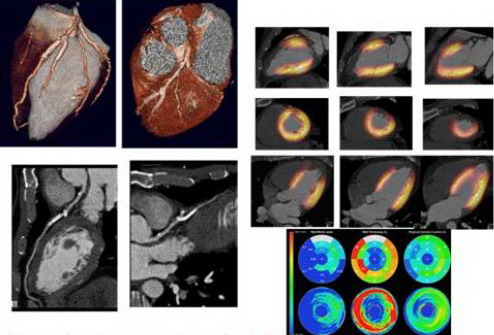

Các ứng dụng của PET và PET/CT trong tim mạch học là ghi

hình tưới máu cơ tim và đánh giá sự sống còn của cơ tim. Ghi hình tưới

máu cơ tim với PET có độ nhạy lớn hơn ít nhưng độ đặc hiệu lớn hơn đáng kể so

với kỹ thuật SPECT. FDG-PET đối với đánh giá sự sống còn của cơ tim làm

tăng tỷ lệ phần trăm biểu hiện bệnh lý cơ tim về chứng thiếu máu cục bộ hoặc

đánh giá sau ghép tim. FDG-PET cũng được chấp nhận rộng rãi là một tiêu chuẩn

vàng đối với đánh giá sự sống còn của cơ tim…

Hình ảnh Bệnh nhân bị nhồi máu cơ tim trước vách và được đặt stent

cấp cứu ở nhánh chéo đầu tiên của động mạch xuống trước trái. Chụp mạch cho thấy

dòng chảy phía sau stent bình thường FDG PET cho thấy không có dấu hiệu cơ tim

còn sống ở vách tim ngoại vi do nhồi máu cơ tim cũ. Phân tích độ dày và chuyển

động của vách tim trên của số CT cho thấy vách cơ tim mỏng và giảm vận động của

vách trước